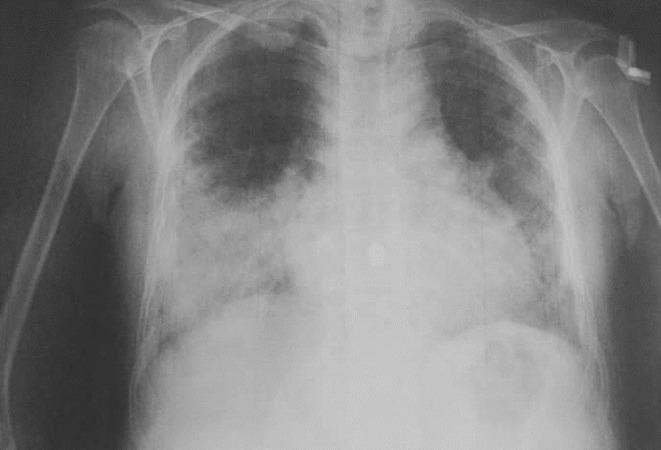

A rare coincidence of Turner syndrome and bronchiectasis: A case report.

Similar to bronchiectasis, Turner syndrome is possible to have more pathological manifestations or etiologies than what has already been documented. Slower recovery process is expected when treating a patient with several comorbidities like Turner syndrome. Turner syndrome patients are vulnerable and should be extensively monitored to lower late presentation rates.